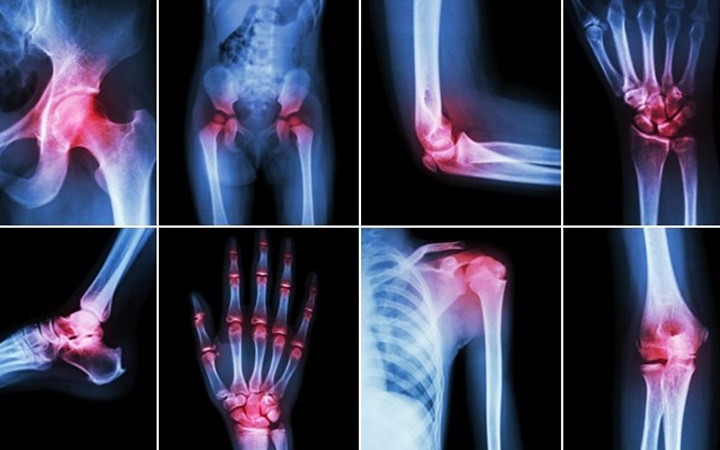

![]() |

| Viêm khớp: Mùa Đông cũng là khắc tinh của những người bị đau khớp. Những người bị viêm khớp cho biết, các khớp xương của họ cứng hơn và bị đau hơn vào mùa Đông. Tuy nhiên, không có cơ sở nào chứng minh rằng thời tiết lạnh hơn sẽ gây ra bệnh đau khớp. Một số chuyên gia cho rằng, con người bị trầm cảm hơn trong thời tiết mùa Đông, khiến họ cảm nhận nỗi đau sâu sắc hơn. Các chuyên gia đưa ra lời khuyên rằng, việc tập thể dục hàng ngày có thể giúp cải thiện thể chất và cả tinh thần của người bệnh. Bơi lội là môn thể thao lý tưởng cho những người có vấn đề về khớp. Ảnh: KT |